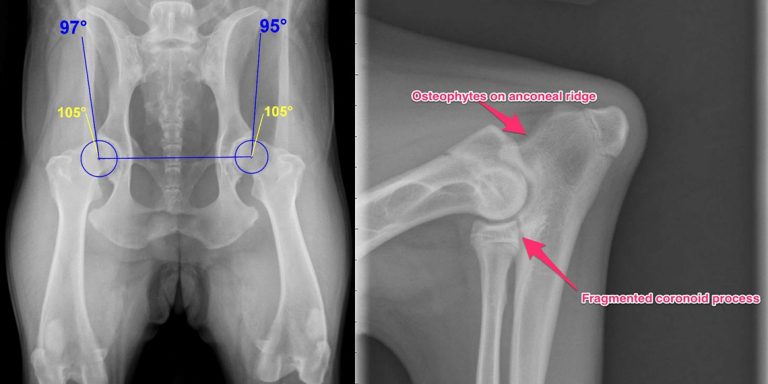

Odată hotărâți și asupra sexului, ne putem duce sa alegem cățelul. În principiu ar fi bine, dacă ne dorim un exemplar de rasă, să mergem la un crescător, care ne poate oferi și pedigree, cunoscând astfel originea cățelului. Este bine să vizitezi canisa sau cuibul, să vezi toți puii, iar dacă este posibil și părinții. Ne interesează actele părinților (pedigree-ul și carnetul de sănătate care trebuie să conțină schema de vaccinare și deparazitările, toate tratamentele și rezultatele testelor medicale – radiografii de sold, teste oftalmologice și alte teste în funcție de bolile specifice rasei). Vârsta minimă la care puiul poate fi scos din cuib este de 8-10 săptămâni, deoarece până la această vârstă puiul își stabilește o ierarhie fată de frați și surori, iar scoaterea lui din cuib poate avea ulterior efecte în comportamentul fată de alți semeni.